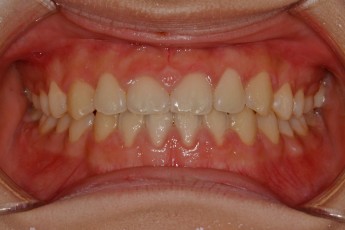

Before

After